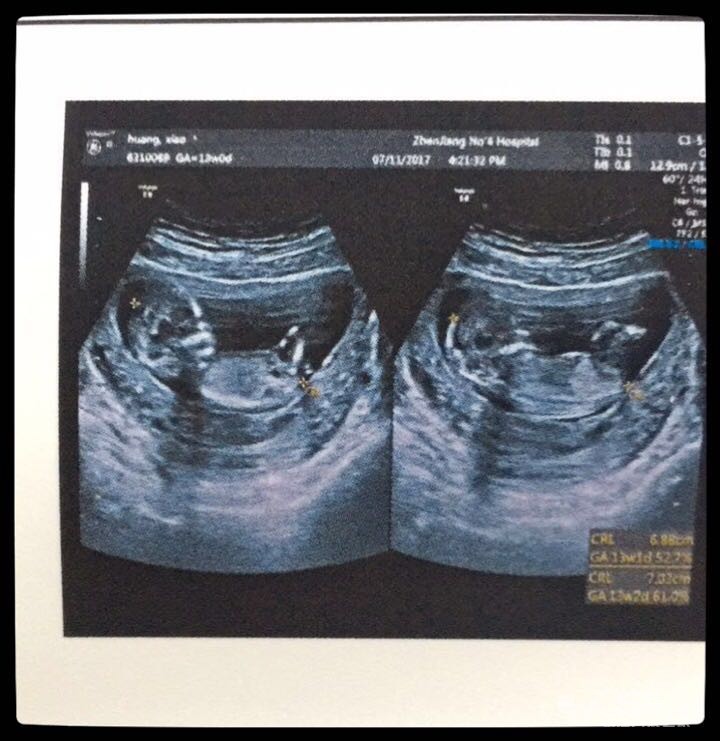

还没做四维呢  先来一张早期的B超镇楼吧

镇楼的那张就是nt照片,nt值2.1,临界点是2.5,正常范围内,就是孩子偏大一周多,医生说大了总比小了好,让我过一个月去产科开始产检。nt到这里,算是圆满结束了